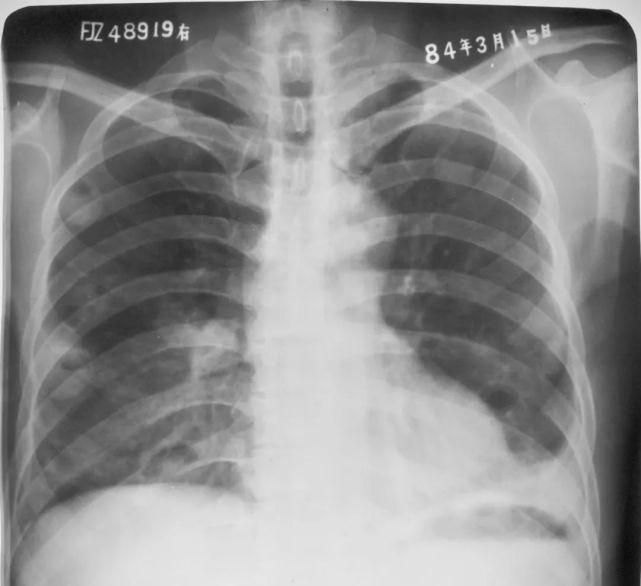

右上、下肺支原体肺炎

图片

胸部正位片示:右上、下肺野肺纹理增粗,可见斑片状阴影,密度较淡,局部呈扇形自肺门部发出(箭头所指)